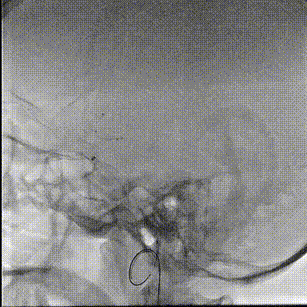

术中缓慢释放NeuroStellar®颅内支架头端后系统稳定,随后释放至支架尾端,造影提示支架打开满意,贴壁满意。

最后经6F中间导管正侧位造影留存影像后结束手术。